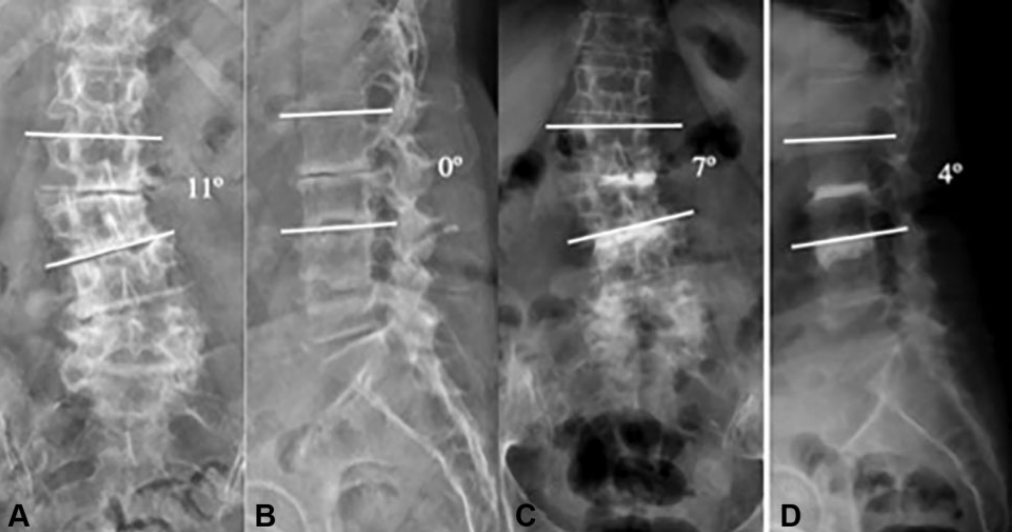

图: 典型的手风琴现象左图为站立位X线片,右图为仰卧位CT。站立位负重时的椎间盘与仰卧位(不负重)椎间盘塌陷程度不同,且侧凸角度也不同(分别为25°和14°)

图: 与典型病例相似的另一退变性侧凸患者,术前存在手风琴现象,经多节段PCD术后冠状位得到10°的纠正且恢复部分腰椎前凸

回顾性分析PCD治疗54例严重椎间盘退变伴/不伴退行性侧凸的病例资料,手术步骤参考上述的技术报道,术后最少随访1年,VAS和ODI评分均显著改善,腰椎前凸和冠状位Cobb角得到部分纠正。平均手术时间38min,平均住院时间1.2天。